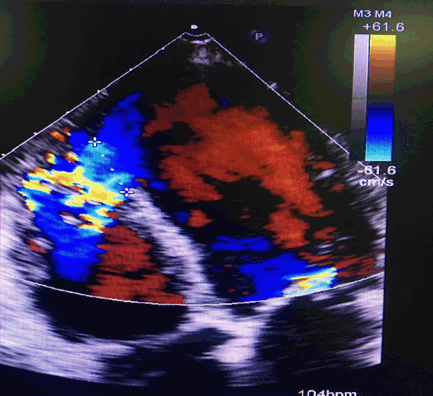

A 72-years old male complaining of sudden onset chest pain was referred to our cardiac centre. ECG was revealed acute inferior ST- segment elevation (STEMI). Relatives denied previous history of any chest pain or CCU admission. The patient was a ex-smoker, diabetic (type I), hypertension with a family history of coronary heart disease (CAD). On physical examination, the patient was restless, and distress. The blood pressure was 80/50 mm Hg, pulse 125 bpm, respiratory rate 24 bpm. His skin was cool and poorly perfused with shallow respiration, and weak peripheral pulses. Laboratory investigations were showing troponin (0.170 ng/mL), serum creatinine level (1.3 mg/dL), and MB-CK level (229 U/L). Coronary angiography was revealed total occluded left descending artery (LAD) and right coronary artery (RCA), and primary PCI was performed. Trans-Thoracic Echography (TTE) demonstrated a VSR (20 mm) located inferior basal and EF < 25% (Figures 1 and 2). Patient was in cardiogenic shock, and intra-aortic balloon pump (IABP) was inserted. Chest X-ray showed increased cardiothoracic ratio with lung congestion. Medical management is aimed to improve cardiac output and reduce shunt. Inotropes, diuretics, and IABP are often used. Patient is hemodynamically stable and still on IABP for 14-days before surgery. Heparin is stopped 6-hours before surgery.

Figure 2. Pre-operative echocardiogram shows a ventricular septal rupture with left-to right shunt flow

Patient was urgently transferred to operative room. Median sternotomy, then cardiopulmonary bypass (CPB) with moderate hypothermia (32 °C) was established after cannulation of aorta, SVC, and IVC with tapes around cavae. IABP was stopped then aortic cross-clamp was placed, and antegrade blood cardioplegic arrest was induced. We made longitudinal incision lateral and parallel to left descending artery (LDA) in left ventricle infarct area. VSR identified in basal apical septum. Stay sutures were placed to expose the edges of the defect (Figure 3). The necrotic tissue was debrided, revealing a defect 2.5 cm. VSR closure without tension employed using a bovine pericardial patch with Teflon felt pledgets placed on RV (Figure 4). Ventriculotomy was closed by double layer buttressed with Teflon felt strips (Figure 5). Tisseel Lyo Sealant used after preparation by Fibrinotherm apparatus to ensure complete hemostasis (Figures 6 and 7). TTE revealed no residual shunt. Patient weaned from CPB smoothly with minimal inotropes and IABP. IABP weaned after 2 days. Patient was discharged from hospital on 10th POD without any event.